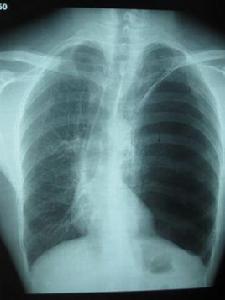

1.1 胸部X線檢查:是診斷肺大泡的最好方法。肺尖部肺大泡表現為位於肺野邊緣甚細薄的透亮空腔,可為圓形、橢圓形或較扁的長方形,大小不一,較大的肺大泡中,有時可見到橫貫的間隔。多個肺大泡靠攏在一起可呈多面狀。一般不與較大支氣管直接相通,無液平,支氣管造影劑也不能進入。肺底部的肺大泡,在正位胸片上常常不易見到,有的可以完全位於膈頂水平之下,有的則僅有部分位於膈頂之上,肺大泡壁如不顯示為連貫的環狀線條影,很易被誤認為幕頂狀胸膜粘連。巨大肺大泡一般具有張力,在其周圍可有一層壓迫性肺不張,使泡壁顯得較厚,貼近胸壁的可不清楚。附近的肺被推壓而引起部分肺不張,肺紋理聚攏,透亮度減低。肺大泡可以相互融合而形成占位很大的肺大泡,形似局限性氣胸。肺大泡也可破裂而產生局限性氣胸。

2.2 X線或CT檢查:肺部有囊泡樣改變,泡中有多數方向不一的條索狀陰影,泡中無肺紋理。囊壁菲薄,有的囊腔中有液氣面。